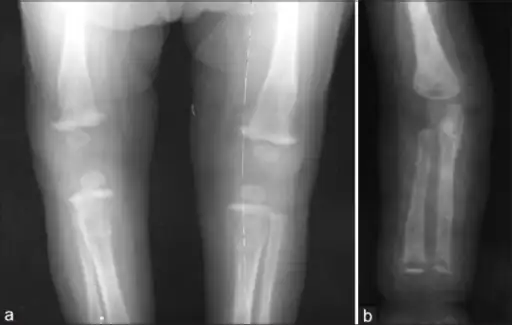

Wimberger corner sign; X-rays of (a) lower limbs (AP view) and (b) upper limbs (AP view) showing resolution of metaphyseal erosions and periosteal reaction

a) X-ray of the lower limb (AP view) showing proximal tibial metaphyseal erosions along with periosteal reaction and (b) X-ray of the upper limb (AP view) showing distal tibial and fibular metaphyseal erosions with periosteal reaction